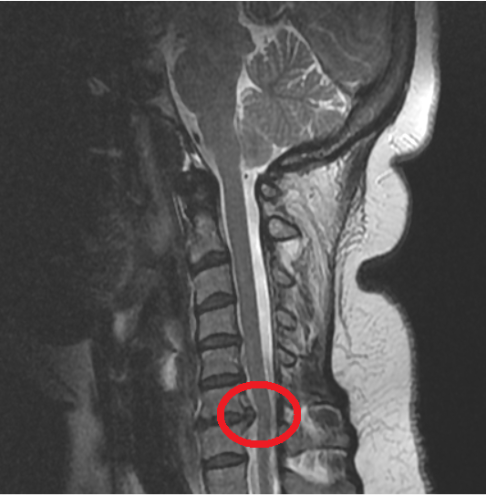

Boyun fıtığı, boyun bölgesindeki (servikal omurga) omurlar arasında bulunan disklerin, dış çeperinin yırtılması sonucu içindeki jelimsi maddenin dışarı çıkmasıdır. Bu durum, omurilik veya sinir köklerine baskı yaparak boyun, omuz ve kol ağrısı, uyuşma veya güç kaybı gibi sorunlara yol açabilir.

En sık C5-C6 ve C6-C7 seviyelerinde görülür, çünkü bu bölgeler hareket açısından daha fazla yük taşır.

- MRG (Manyetik Rezonans Görüntüleme): Disk yapısındaki hasarı ve sinir köklerine baskıyı gösterir.